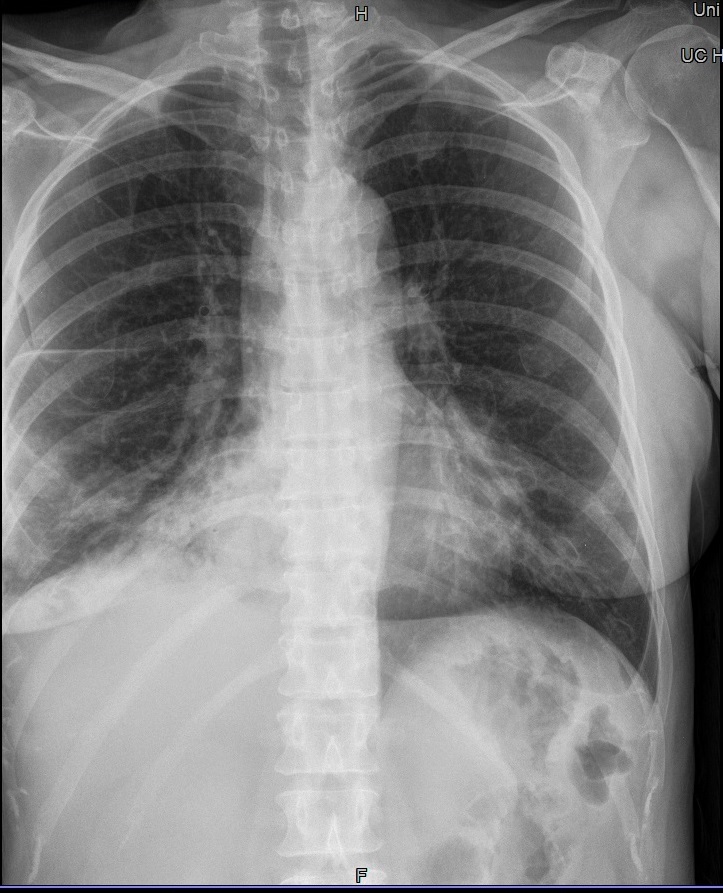

Fehler

Rippen 7-9 werden vom Kassettenrand abgeschnitten. Eine Beurteilung ob die Kortikalis intakt ist, kann hier nicht getroffen werden.

Abhilfe

Patient besser auf der Kassette lagern und schauen, dass beim Atemkommando nicht die Rippen über die Kassette ragen. Sollte das alles nichts bringen evtl. auch auf eine größere Kassette zurückgreifen.